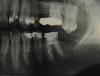

Мария Иванова Опубликовано 10 октября, 2013 Поделиться Опубликовано 10 октября, 2013 (изменено) Здравствуйте! Помогите пожалуйста разобраться, кому верить? На днях отломилась тонкая стенка с внутренней стороны зуба и чуть позже вылетела давно поставленная пломба на много лет назад депульпированном нижнем левом 6 коренном зубе.На консультации ортопед предложил ставить коронку, так как от зуба осталась всего одна тонкая стенка с наружной стороны, а рентген показал, что корни зуба хорошие. В понедельник (7.10.13), установили 2 штифта из стекловолокна и нарастили зуб, чтоб потом на него ставить коронку из металлокерамики. Работала стоматолог торопясь, то сверло выпало из рук, то второй подготовленный штифт исчез бесследно, потом ей что-то в глаз попало при сверлении.. .Жевать этим зубом твердую пишу первые 3 дня было больно. Стоматолог объясняет тем, что мол это идет привыкание организма к штифтам, назначила лазер и полоскать рот раствором из соли и соды. Сказала, надо подождать примерно недельку, чтоб нарощенный зуб привык к давлению от твердой пищи. Примерно так...В среду (9.10.13) съездила на консультацию по поводу зуба к другому стоматологу, сделала ортопантомограммный снимок. Он сказал, что зуб надо заново перелечивать и теперь это будет дольше и сложнее после работы того, кто ставил штифты. Кстати, второму доктору у меня больше доверия как к врачу, жалею что к нему сразу не пошла лечиться.Теперь. Пошел 4-ый день после установки и жевать действительно стало не так больновато.Надо ли перелечивать зуб?Извините за качество, снимки к сожалению пока только отсканированные, если плохо видно, вечером попробую сфотографировать и выложить как положено. Изменено 10 октября, 2013 пользователем Мария Иванова Ссылка на комментарий

DmitrySH Опубликовано 10 октября, 2013 Поделиться Опубликовано 10 октября, 2013 Снимки не очень.. оба шестые слева нужно лечить Ссылка на комментарий

DmitrySH Опубликовано 10 октября, 2013 Поделиться Опубликовано 10 октября, 2013 Дмитрий, а последние загруженные снимки, там получше видно?Мне бы сейчас с нижним шестым разобраться.. То есть все таки, нижний надо перелечивать, по -Вашему? не совсем, но лучше. На "заднем" корне есть очаг воспаления. конечно стараться перелечить. да еще вверху на всех передних зубах избавиться от кариеса + в зубе 22 нужна ревизия канала Ссылка на комментарий

anvladd Опубликовано 11 октября, 2013 Поделиться Опубликовано 11 октября, 2013 (изменено) Объясните пожалуйста, зачем вкладка? 2 штифта сверху покрывались пломбой из светоотражающего материала, потом сразу планировалось закрыть металокерамич.коронкой. Значит, при перелечивании корней потом дополнительно попросить у врача для надежности еще сделать вкладку? Мне бы сейчас его перелечить осторожно, чтоб совсем без корней не остаться и буду это делать в другой частной клинике. штифты вытащить!!!,каналы перелечить и сделать вкладку+коронку,что не понятно? На заднем корне очаг воспаления расположен снизу или верху, в смысле ближе к десне или наоборот к надкостнице? Врач, к которому ездила на консультацию и у которого теперь хочу перелечивать, говорил что-то про глубокий кариес на корнях зуба, боюсь теперь... Извините за глупый вопрос, это воспаление же не вылечить лазером? Все не пойму, зачем первый врач мне лазер назначила. За консультацию по другим зубам очень Вам благодарна..очаг воспаления больше в области верхушки дистального(заднего)корня Изменено 11 октября, 2013 пользователем anvladd Ссылка на комментарий